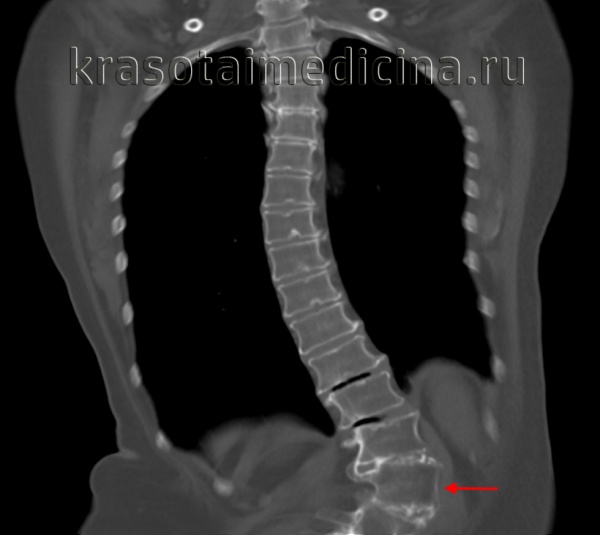

Рентгенограмма позвоночника при сколиозе

Сколиоз у детей. Стойкая деформация позвоночного столба, характеризующаяся его боковым отклонением и торсией. Сколиоз у детей сопровождается асимметричным положением надплечий, лопаток и других костных ориентиров, перекосом таза, деформацией грудной клетки, нарушениями со стороны внутренних органов. Для диагностики сколиоза у детей выполняются полипозиционные рентгенограммы позвоночника с расчетом величины искривления. Консервативное лечение сколиоза у детей включает ортопедический режим, массаж, корригирующую гимнастику, физиотерапию, ношение ортопедического корсета; по показаниям производится хирургическая коррекция сколиоза.

Раннее выявление сколиоза – важнейшая задача диспансерных осмотров детей дошкольного и школьного возраста педиатром, детским хирургом, неврологом, детским ортопедом. Для правильной оценки осанки необходимо последовательное обследование ребенка в положении стоя (спереди, сбоку, сзади), сидя и лежа. При этом обращают внимание на высоту надплечий, асимметрию кожных складок, лопаток, таза, наличие реберного горба и другие признаки сколиоза у детей. Степень искривления позвоночника в градусах определяют с помощью сколиозометра. Выявление отклонения позвоночника более чем на 5-7°, является основанием для проведения рентгенографии ребенку.

Рентгенография позвоночника выполняется в положении стоя и лежа в 2-х проекциях. На основании полученных спондилограмм производится расчет величины искривления по методике Фергюссона или Кобба, определение индекса стабильности позвоночника. Для более детального обследования интересующего отдела позвоночника может применяться рентгеновская томография, MРТ или КТ позвоночника, миелография. Для обследования и динамического наблюдения детей предпочтительнее применять нелучевые методы исследования, например, компьютерную оптическую топографию. Обязательным компонентом диагностики сколиоза у детей является фотографирование ребенка с различных точек на всех этапах наблюдения.